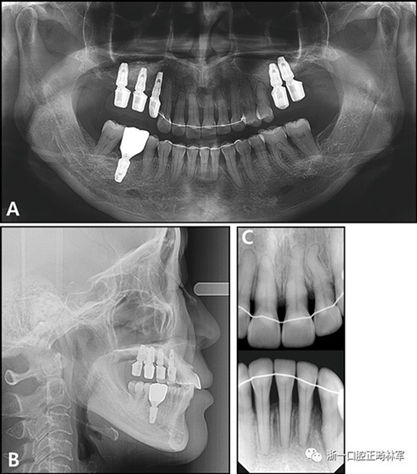

治療后全景X線片顯示與初始值相比,沒有顯著的骨喪失。上頜尖牙被推入并向遠中移動,導(dǎo)致在根尖周觀察到尖牙骨水平的改善。在拔除的下頜側(cè)切牙周圍出現(xiàn)嚴重的牙槽骨缺損,并且尖牙近中側(cè)的牙周病引起了骨內(nèi)缺損。在關(guān)閉間隙期間,下頜中切牙和尖牙被移向了骨質(zhì)缺損區(qū)域,并且側(cè)切牙周圍的缺損已被恢復(fù)(圖12)。此外,尖牙的牙齦退縮臨床上也得到了改善(圖13)。

圖12.治療后的X線片:A,全景X光片;B,頭影側(cè)位片;C,根尖片

治療后頭影測量分析顯示上頜切牙的傾斜和唇部相對于E線的位置都得到改善(表II)。治療前后頭影測量圖的疊加顯示上頜和下頜切牙的向后移動伴隨著上頜切牙的推入。垂直維度在跨學(xué)科正畸綜合治療后被保持。三維模型的疊加顯示了上頜牙列的遠中移動,下頜前牙的回縮和上頜右側(cè)尖牙的推入(圖14)。

根據(jù)治療前后的根尖X光片,可以發(fā)現(xiàn)存在3.5mm顯著改善的放射線骨水平(圖15),并且臨床上牙周袋深度減少(表IV)。此外,力的推入性成分在向遠中移動期間誘導(dǎo)了上頜切牙的推入,并且在根尖X線照片上看到牙槽骨水平的改善。同時,如果種植體首先定位在磨牙區(qū)域,則可以通過使用種植體的臨時修復(fù)作為支抗來控制該力學(xué)過程。這種方法的優(yōu)點在于它解決了患者的主訴,即通過逆轉(zhuǎn)上頜前牙的張開和用最小程度的外科手術(shù)取代缺失的后牙進行咬合來重建咬合和美學(xué)。但是當(dāng)施加推入力時,在力作用線上施加一個垂直方向的力是不利的。完成整個治療需要花費很多時間,并且在正畸治療期間臨時修復(fù)體可能被破壞。